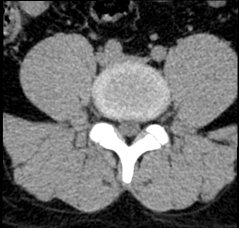

Chẩn đoán hình ảnh mô mềm tiên tiến cho vùng bụng.

Tăng cường độ tương phản I-ốt.

Hỗ trợ đánh giá an toàn cho bệnh nhân.

Đảm bảo hình ảnh chất lượng cao.